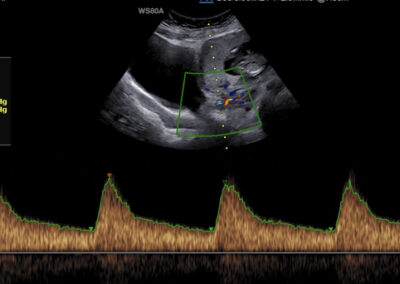

Genetický ultrazvuk Fetální echokardiografie Dopplerovské vyšetření krevního oběhu miminka a placenty Screening předčasného porodu Screening preeklampsie a zaostávání růstu miminka Vyšetření vícečetných těhotenství 3D-4D ultrazvuk Určení pohlaví miminka